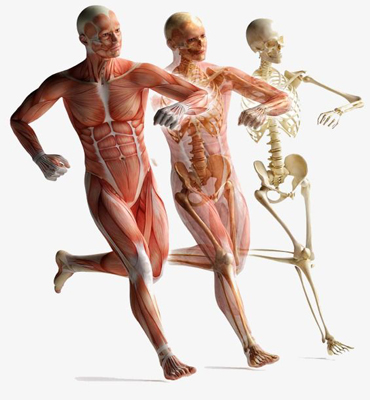

Joint Problems

- Spondylitis

- OstoArthritis

- Rheumatoid Arthritis

- Gout - Gouty Arthritis

- Spondylosis

- Vertebral Disc Problems

- Old age Degenerative changes